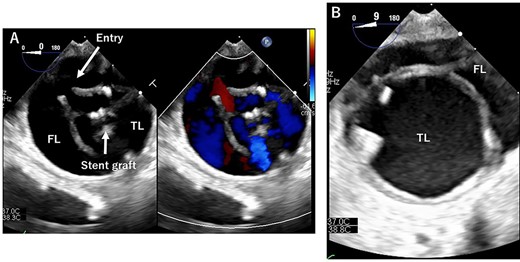

TEE during the operation. (A): At entry site. Entry and stent grafts are shown. FL, false lumen; TL, true lumen. (B): Expansion of the TL.

TEVAR was performed through the right femoral artery (rFA) with cut-down. Pulsation was not observed; therefore, we confirmed that the rFA was not dissected using echography from the surface. A 5Fr sheath (Medikit Super Sheath, Medikit, Tokyo, Japan) and 0.035-inch guidewire (Radifocus, Terumo, Tokyo, Japan) were inserted carefully, and we confirmed it in the true lumen using transesophageal echography (TEE) during the operation (Fig. 2A). Subsequently, a 5Fr pigtail catheter (Medikit, Tokyo, Japan) was inserted, and the guidewire was changed to a stiff wire (Lunderquist extra-stiff guidewire, Cook, Bloomington, IN, USA). Then, a 20 Fr Dryseal sheath (WL Gore and Associates, Flagstaff, AZ) was inserted. Through the sheath, we deployed Conformable TAG (26 mm × 100 mm; WL Gore and Associates, Flagstaff, AZ) at the descending aorta. Next, we deployed Conformable TAG (26 mm × 150 mm; WL Gore and Associates, Flagstaff, AZ) just distal to the left subclavian artery to the first stent graft with sufficient overlap. At this point, we observed expansion of the true lumen with TEE (Fig. 2B). Finally, we placed the Zenith Dissection Bare stent (36 mm × 164 mm; Cook, Bloomington, IN) at the distal end of the second stent graft with one stent overlap (Fig. 3). We confirmed the improvement of malperfusion and no access trouble.